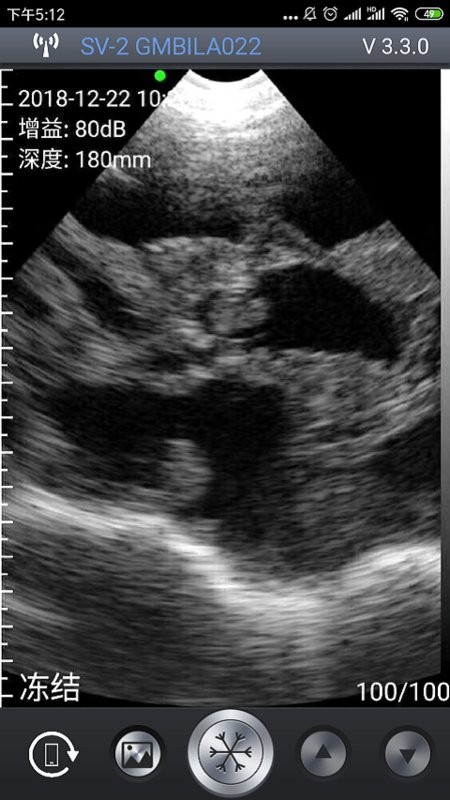

5、图片成像:

通过最强大的成像功能也是能让你查看到最全面的重要信息内容,任何图片信息都能够以最全面的方式为您介绍;

智能b超手机版是一款针对养殖业提供的b超检测工具,通过连接设备,手机拍摄的方式,展示图像信息,即时进行b超诊断,随时查看诊断数据,一目了然,轻松了解,操作简单,有助于解决各种各样的养殖问题,便于养殖人进行养殖工作!

智能B超 App与北京索诺普科技开发的无线兽用B超仪一起构成一套方便,高效的养殖业B超诊断系统。无线智能B超,是养猪人的绝佳工具,为您开启轻松工作的一天。